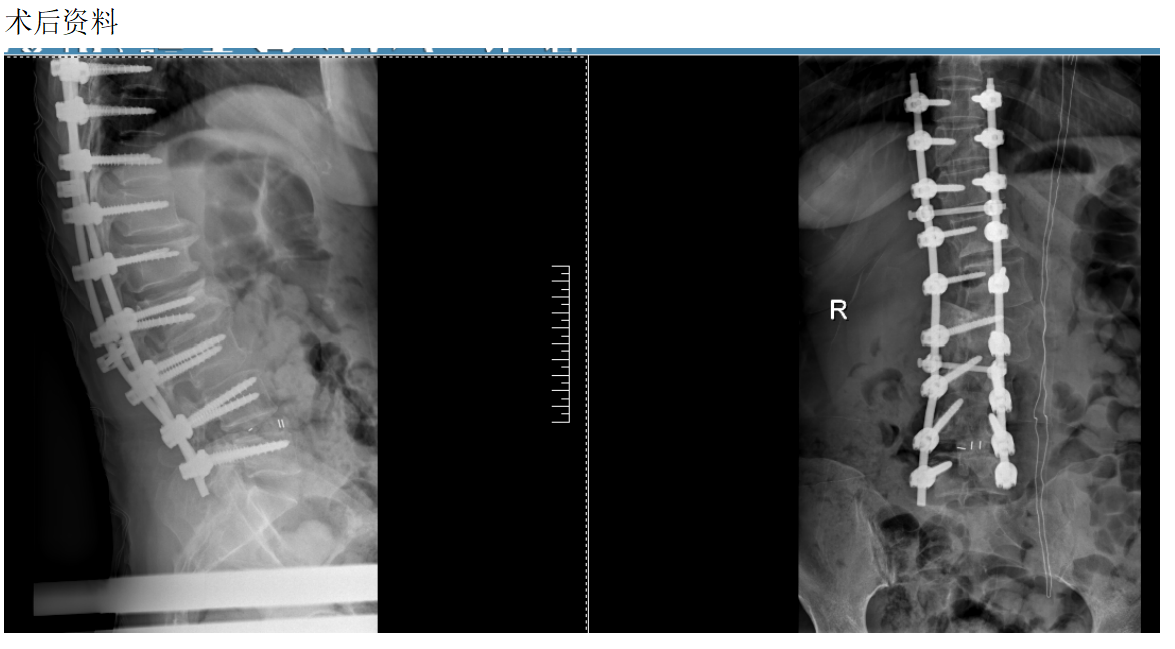

现病史:患者20天前劳累后出现腰痛及右下肢放射痛,疼痛沿右侧臀部向右足放射,伴有酸胀及麻木。其症状加重,活动受限,步行困难,在当地诊所就诊,按按摩、针灸等理疗及口服药物等治疗,效果欠佳。今日为求进一步诊治,来我院椎间盘科,腰椎CT示:1.L3/L4椎间盘膨出并突出、钙化,继发性水平椎管狭窄;2.L4/L5椎间盘膨出并突出,继发性水平椎管狭窄;3.腰椎侧弯;腰椎退行性改变,S1隐性脊柱裂。以“脊柱侧弯畸形,腰椎间盘突出症”为诊断收住我科。发病以来,神志清楚,精神尚可,饮食正常,睡眠一般,体力正常,大小便正常。